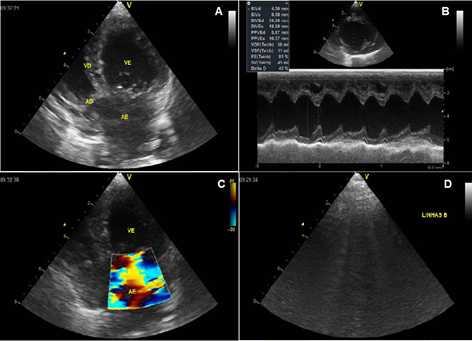

The Doppler echocardiography revealed the presence of mitral valve degeneration with prolapse of the septal leaflet and countless B lines in the right and left hemithorax (Figure 2A–2C).

Figure 2 Doppler echocardiography of heart. A. Degenerative disease of mitral valve. B. Echodopplercardiography and spectral doppler of mitral valve. Mitral valve showing a degenerative appearance with prolapse of septal leaflet. 2C. Doppler study and color flow mapping demonstrate significant insufficiency. 2D. Presence of countless B lines in the right and left hemithorax.

The doppler echocardiography is essential for confirming structural and functional changes in the heart of dogs with suspected left heart disease.13

The presence of degenerative disease of mitral valve (valve prolapse) with significant hemodynamic repercussion was observed in the doppler echocardiogram. The B lines were also observed, characterized vertical artifacts, perpendicular to the pleural line that move along the pleural line, generally erasing the A lines. They reflect the filling of the inter and/or intralobular septa associated with pulmonary edema or interstitial lung disease.14